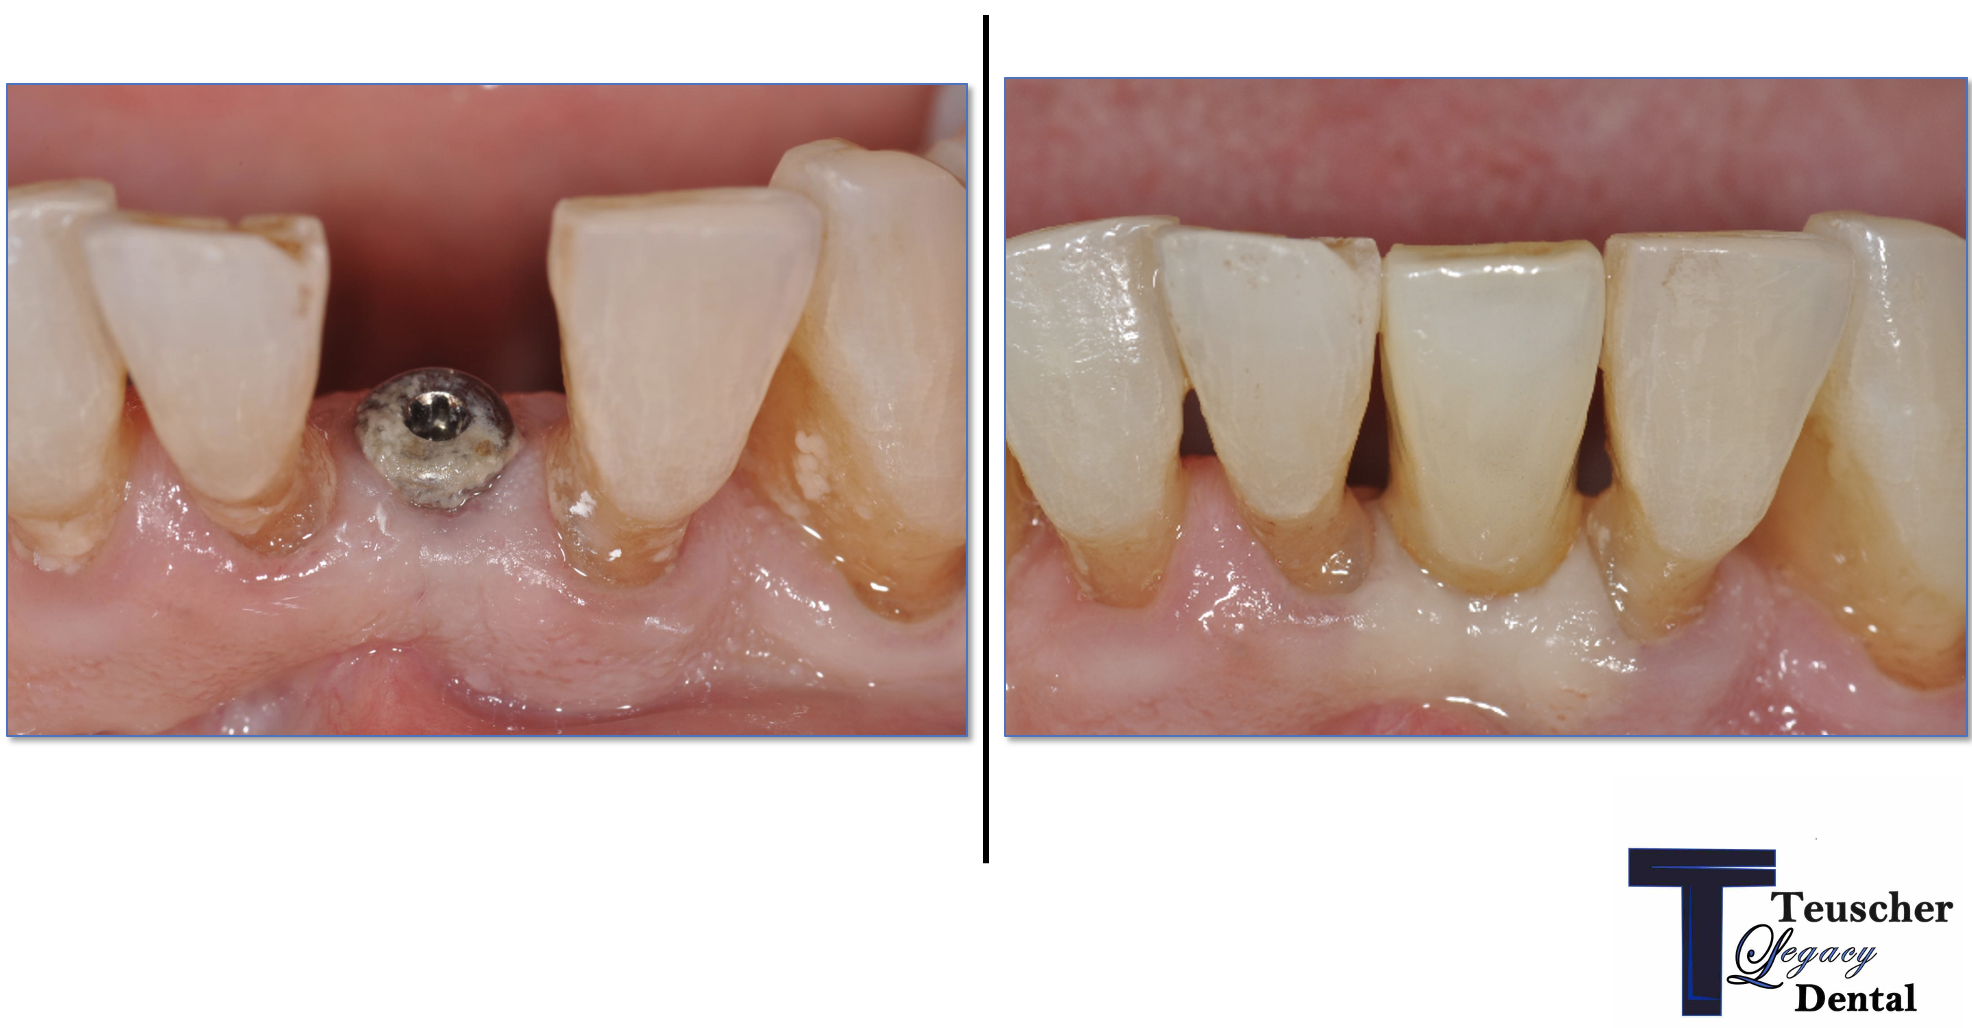

How We Restored a Front Tooth with a Dental Implant — Start to Finish

When it comes to your smile, the front teeth do all the talking.

They’re what people notice first. So when a front tooth is missing or damaged — whether from trauma, decay, or failed restorations — it’s not just about replacing it. It’s about doing it perfectly in the smile.

In this case study, we’ll walk you through one of the more complicated — and rewarding — procedures we do at our practice: a front tooth dental implant. You’ll see how much thought, planning, and precision goes into restoring one small tooth… and why every step in the dental implant process matters.

This first step also helps make sure the patient is on the same page with what to expect a final result to look like. We also go over financial details and timeline. This way the patient knows what to expect every step of the way!CBCT 3D Planning

Often using a guided technique (with a 3D printed surgical guide), we place the implant with extreme precision. It must sit in a position that supports both the future crown and the surrounding gum tissue for a natural look. The exact location is already planned prior to surgery in our CBCT software.Provisional Tooth (Temporary)

In the front of the mouth, we never leave a visible gap. A temporary tooth (provisional) is placed to shape and support the gum tissue during healing. This sculpting phase is key for a beautiful final result. I didn’t go into detail on this in our video. There are various ways to do this while the implant heals though, including a removable partial denture, an essix retainer, or immediately loading the implant with a temporary crown.Healing & Monitoring

Over the next few weeks or months, we monitor soft tissue healing. Sometimes we adjust the temporary to guide gum shaping. Patience here pays off — rushing this stage can lead to esthetic failure. One of the biggest risks in front teeth implants is gum recession!Final Crown

Once everything is stable, we place the final custom crown. Shade, translucency, shape, and surface texture are all matched to your natural teeth so the implant blends in seamlessly.